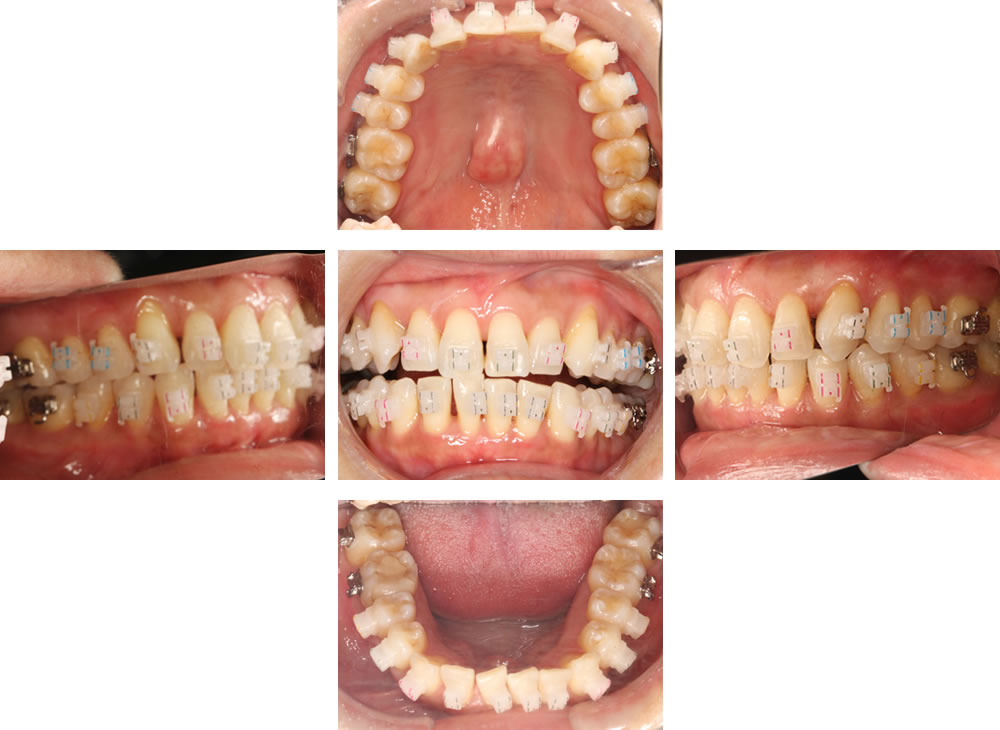

術前では、上下顎の正中がズレていて、平面が斜めの歯並びでした。術後は、上下の正中が揃い、理想的な被蓋関係で噛んだ、キレイな歯並びになりました。

拡大が終了して、ホワイトブラケットを装着したところです。ブラケットを識別するための色が付いていますが、すぐに消えます。

術前では、歯が重なるように乱れた歯並びでしたが、術後は理想的に並んだキレイで大きなアーチになりました。